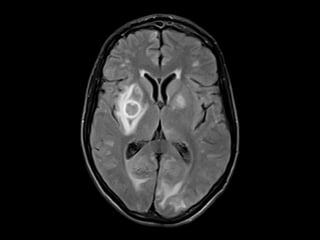

RNM de crânio: lesões multifocais supra e

infratentoriais sugestivas de processo

infeccioso/inflamatório relacionado à infecção

oportunista (neurotoxoplamose).

Demais exames sem alterações, incluindo líquor

e sorologia para toxo.

Caso Clínico RNM decrânio: lesões multifocais supra e infratentoriais sugestivas de processo infeccioso/inflamatório relacionado à infecção oportunista (neurotoxoplamose). Demais exames sem alterações, incluindo líquor e sorologia para toxo.